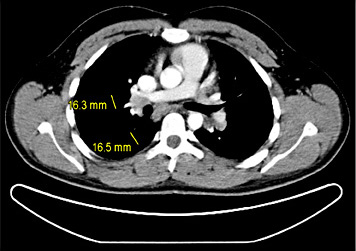

5th patient: this 23-year-old man underwent orchiectomy for marker-negative testicular seminoma at another institution. CT revealed intrathoracic nodules suspicious for mediastinal lymph node metastases. Accordingly, 4 cycles of BEP chemotherapy were administered. Restaging revealed unchanged mediastinal lymphadenopathy (Fig. 4). Then, the patient was referred to our institution for further management. Thorough pulmonological examination including transbronchial biopsy disclosed sarcoidosis-like lymphadenopathy, and thus metastatic disease was excluded. In view of these results, it must retrospectively be assumed that this patient had sarcoidosis synchronously with seminoma rather than having metastatic disease. Accordingly, the serum miR371a-3p level was RQ = 0.0 at the time of re-staging after chemotherapy. Unfortunately, no miR-levels were measured at the time of first presentation. Although speculative, one would assume that miR371a-3p levels had probably been low after orchiectomy for seminoma because the mediastinal lymphadenopathy had not changed ever since. By retrospective consideration, the normal marker level would have indicated the absence of metastases at the outset and accordingly, the patient could have been spared unwarranted chemotherapy and excessive diagnostic procedures apart from emotional distress from extended treatment.

Chest CT of patient #5 after 4 cycles of cisplatin-based chemotherapy: hilar lymphadenopathy. Transbronchial biopsy revealed sarcoidosis.